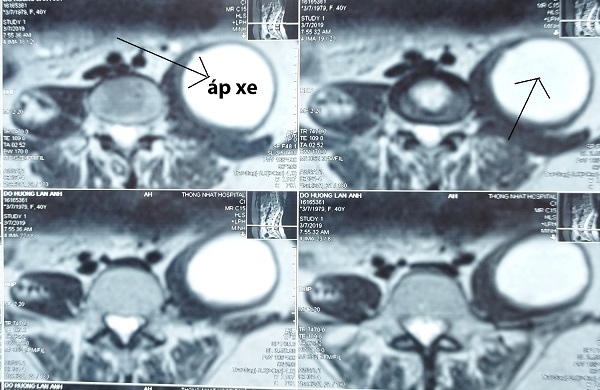

Kết quả chụp MRI tại Bệnh viện Quốc tế City cho thấy, bệnh nhân N.A bị lao cột sống 4 đốt D11-D12, L1-L2, có khối áp xe to dọc cơ thắt lưng chậu trái, được chỉ định phẫu thuật tránh biến chứng.

Hình chụp MRI áp xe cơ thắt lưng chậu của bệnh nhân.